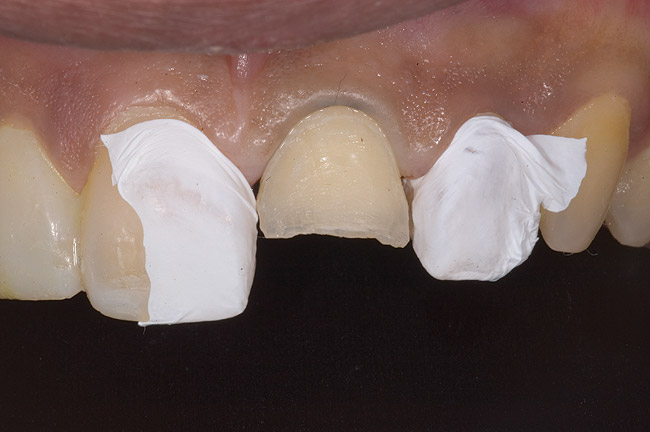

Figure 9: Tooth No. 9 minimally prepared for resin layering on the labial surface.

Figure 9

During the next appointment, a palatal index of the approved provisional was fabricated with putty silicone. This enabled the clinician to precisely build the lingual surfaces and incisal edges of teeth Nos. 6 through 11. The provisional mock-up resin on No. 9 was removed, and the underlying labial tooth was roughened with an abrasive diamond bur. No tooth structure was removed from the palatal surface, and unsupported enamel was rounded off from the labial. An ultrathin dry cord was placed in the gingival sulcus on No. 9 (Figure 9 and Figure 10). Teflon tape was used to isolate No. 9 from adjacent teeth. Then 37% phosphoric acid was used to totally etch the labial surface for 10 seconds and the palatal surfaces on No. 9 for 5 seconds. Single bond was applied and spread uniformly across the tooth and light-cured for 20 seconds.